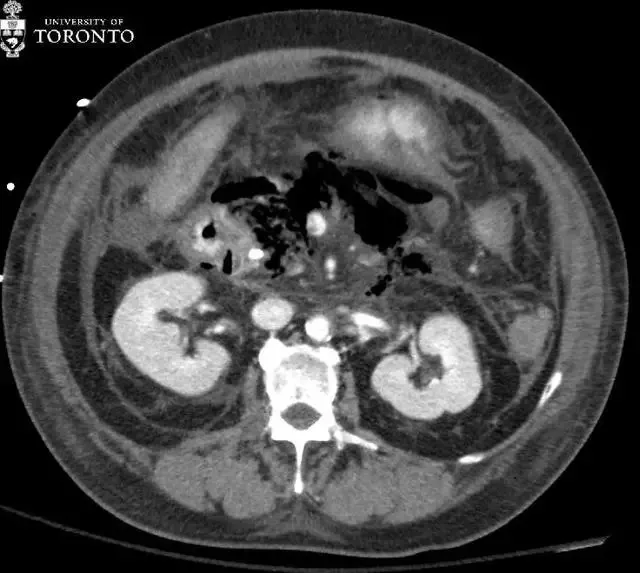

该患者被送入重症监护室 , 并给予高剂量抗生素静脉滴注 。 之后患者病情稳定 , 未进行手术治疗 。 两个星期后 , 患者白细胞计数升高 , 再次昏厥 。 入院当天的 CT 扫描显示广泛的胰腺坏死 。 胰腺组织几乎完全由气泡(红色箭头)所取代 。

诊断:患者被确诊为急性坏死性胰腺炎 , 且可能合并感染 。

为了评估胰腺炎的严重程度 , 通常应用多相流 CT (平扫 , 晚动脉期和静脉期) 。 急性胰腺炎的症状包括胰腺和胰周脂肪间隙的肿胀 。 其并发症包括静脉血栓形成 , 假性动脉瘤 , 腹膜后脓肿(可形成假性囊肿) , 胰腺坏死和感染 。

CT 是诊断胰腺坏死最好的方法 。 不增强的胰腺组织一般被认为是坏死 , 并且坏死的程度与疾病及预后的严重程度相关 。 胰腺坏死感染通常在症状发作后的前四个星期出现 。 约 40%到 70%的坏死性胰腺炎患者会发展为感染坏死 。 感染性胰腺坏死的患者通常病情较重且有中毒症状 , 预后较差 。

从历史经验上看 , 推荐早期积极进行手术清创 , 但延迟干预和导管引流已经表现出改善病情的效果 。 在 CT 上 , 出现气泡则提示感染 , 但仅有 15%的病例会出现 。 因此 , 对于感染坏死的诊断 , 临床和影像相结合是很有必要的 。